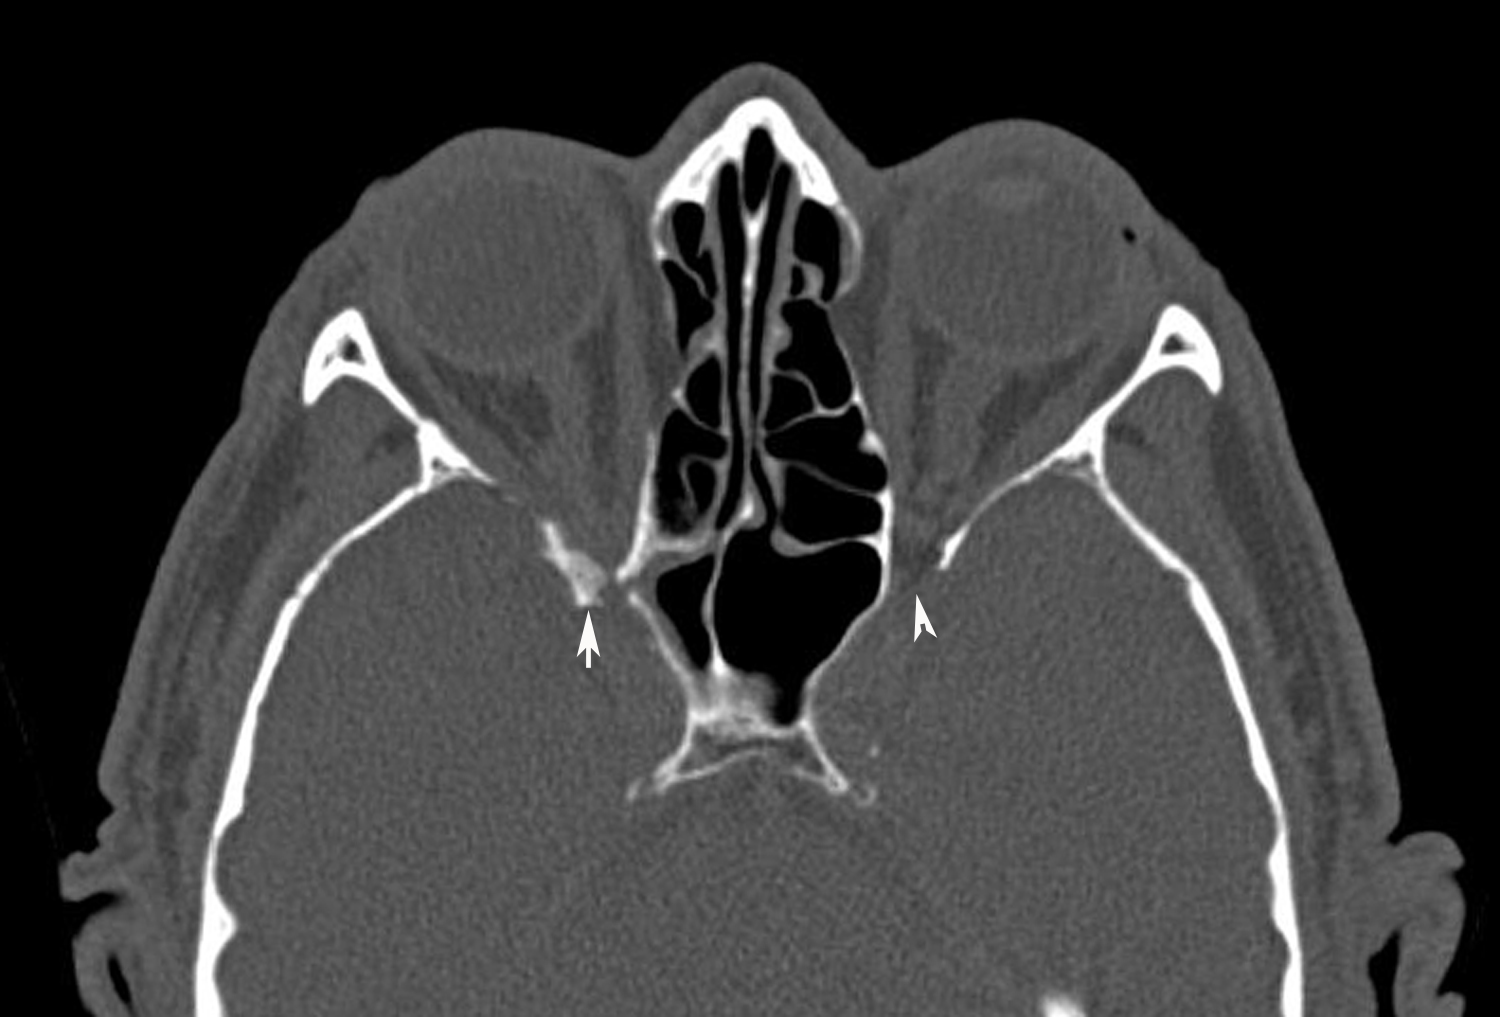

Brain CT Scan showing enlarged and tortuous optic nerve sheathes... Download Scientific Diagram Can Ct Scans Pick Up Nerve Damage A ct scan may be recommended if a patient can’t have an mri. what are the differences between an mri and ct scan? You can see if there’s injury or. ct or mri scans can look for herniated disks, pinched nerves, also called compressed nerves, growths or other problems. radiological imaging is a crucial tool in the. Can Ct Scans Pick Up Nerve Damage.